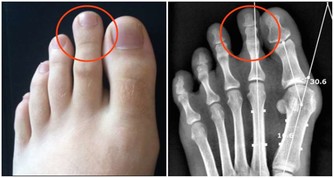

糖尿病足:高血糖導致下肢血管、神經系統病變,一旦皮膚稍有破損、感染而不及時感知或治療,將會迅速形成潰瘍、壞疽,最終不得不做截肢處理,造成病人身體上、心理上雙重打擊,生活質量大大下降,嚴重的甚至還會危及生命。